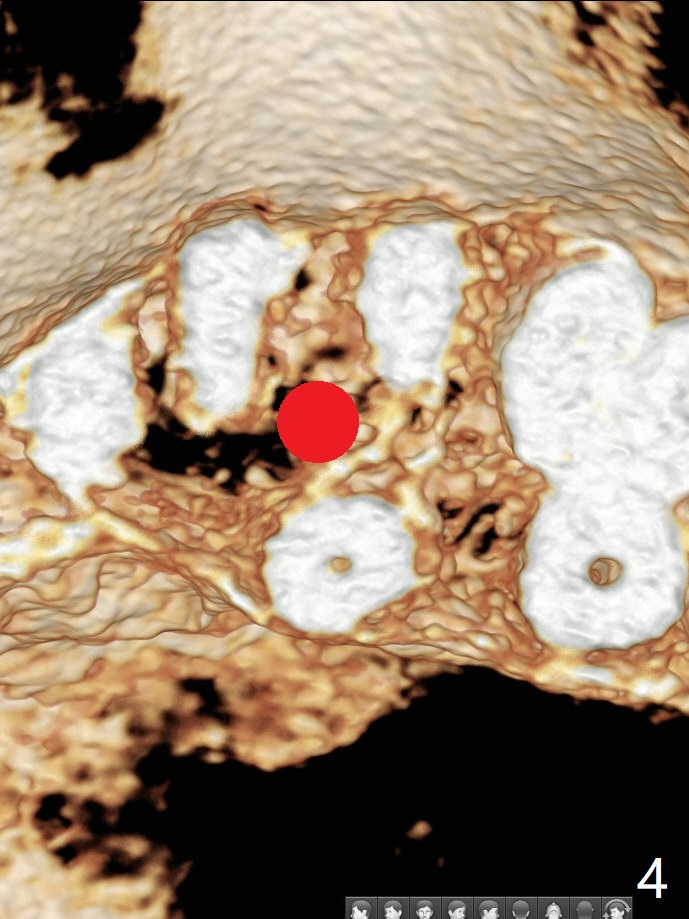

44岁女左上6远中深龋(图一:*),同意拔除种植(图二),由于近中,远中牙槽嵴不等(*),为了增加冠根比例,植体可以种浅些(箭头),但是远中多放置骨粉(红色)。为了防止钻头偏移中隔,去除牙冠(图三),保留牙根情况下,完成钻洞(图四:红色),然后拔除牙根(图五:黑色),放置植体(绿色)。